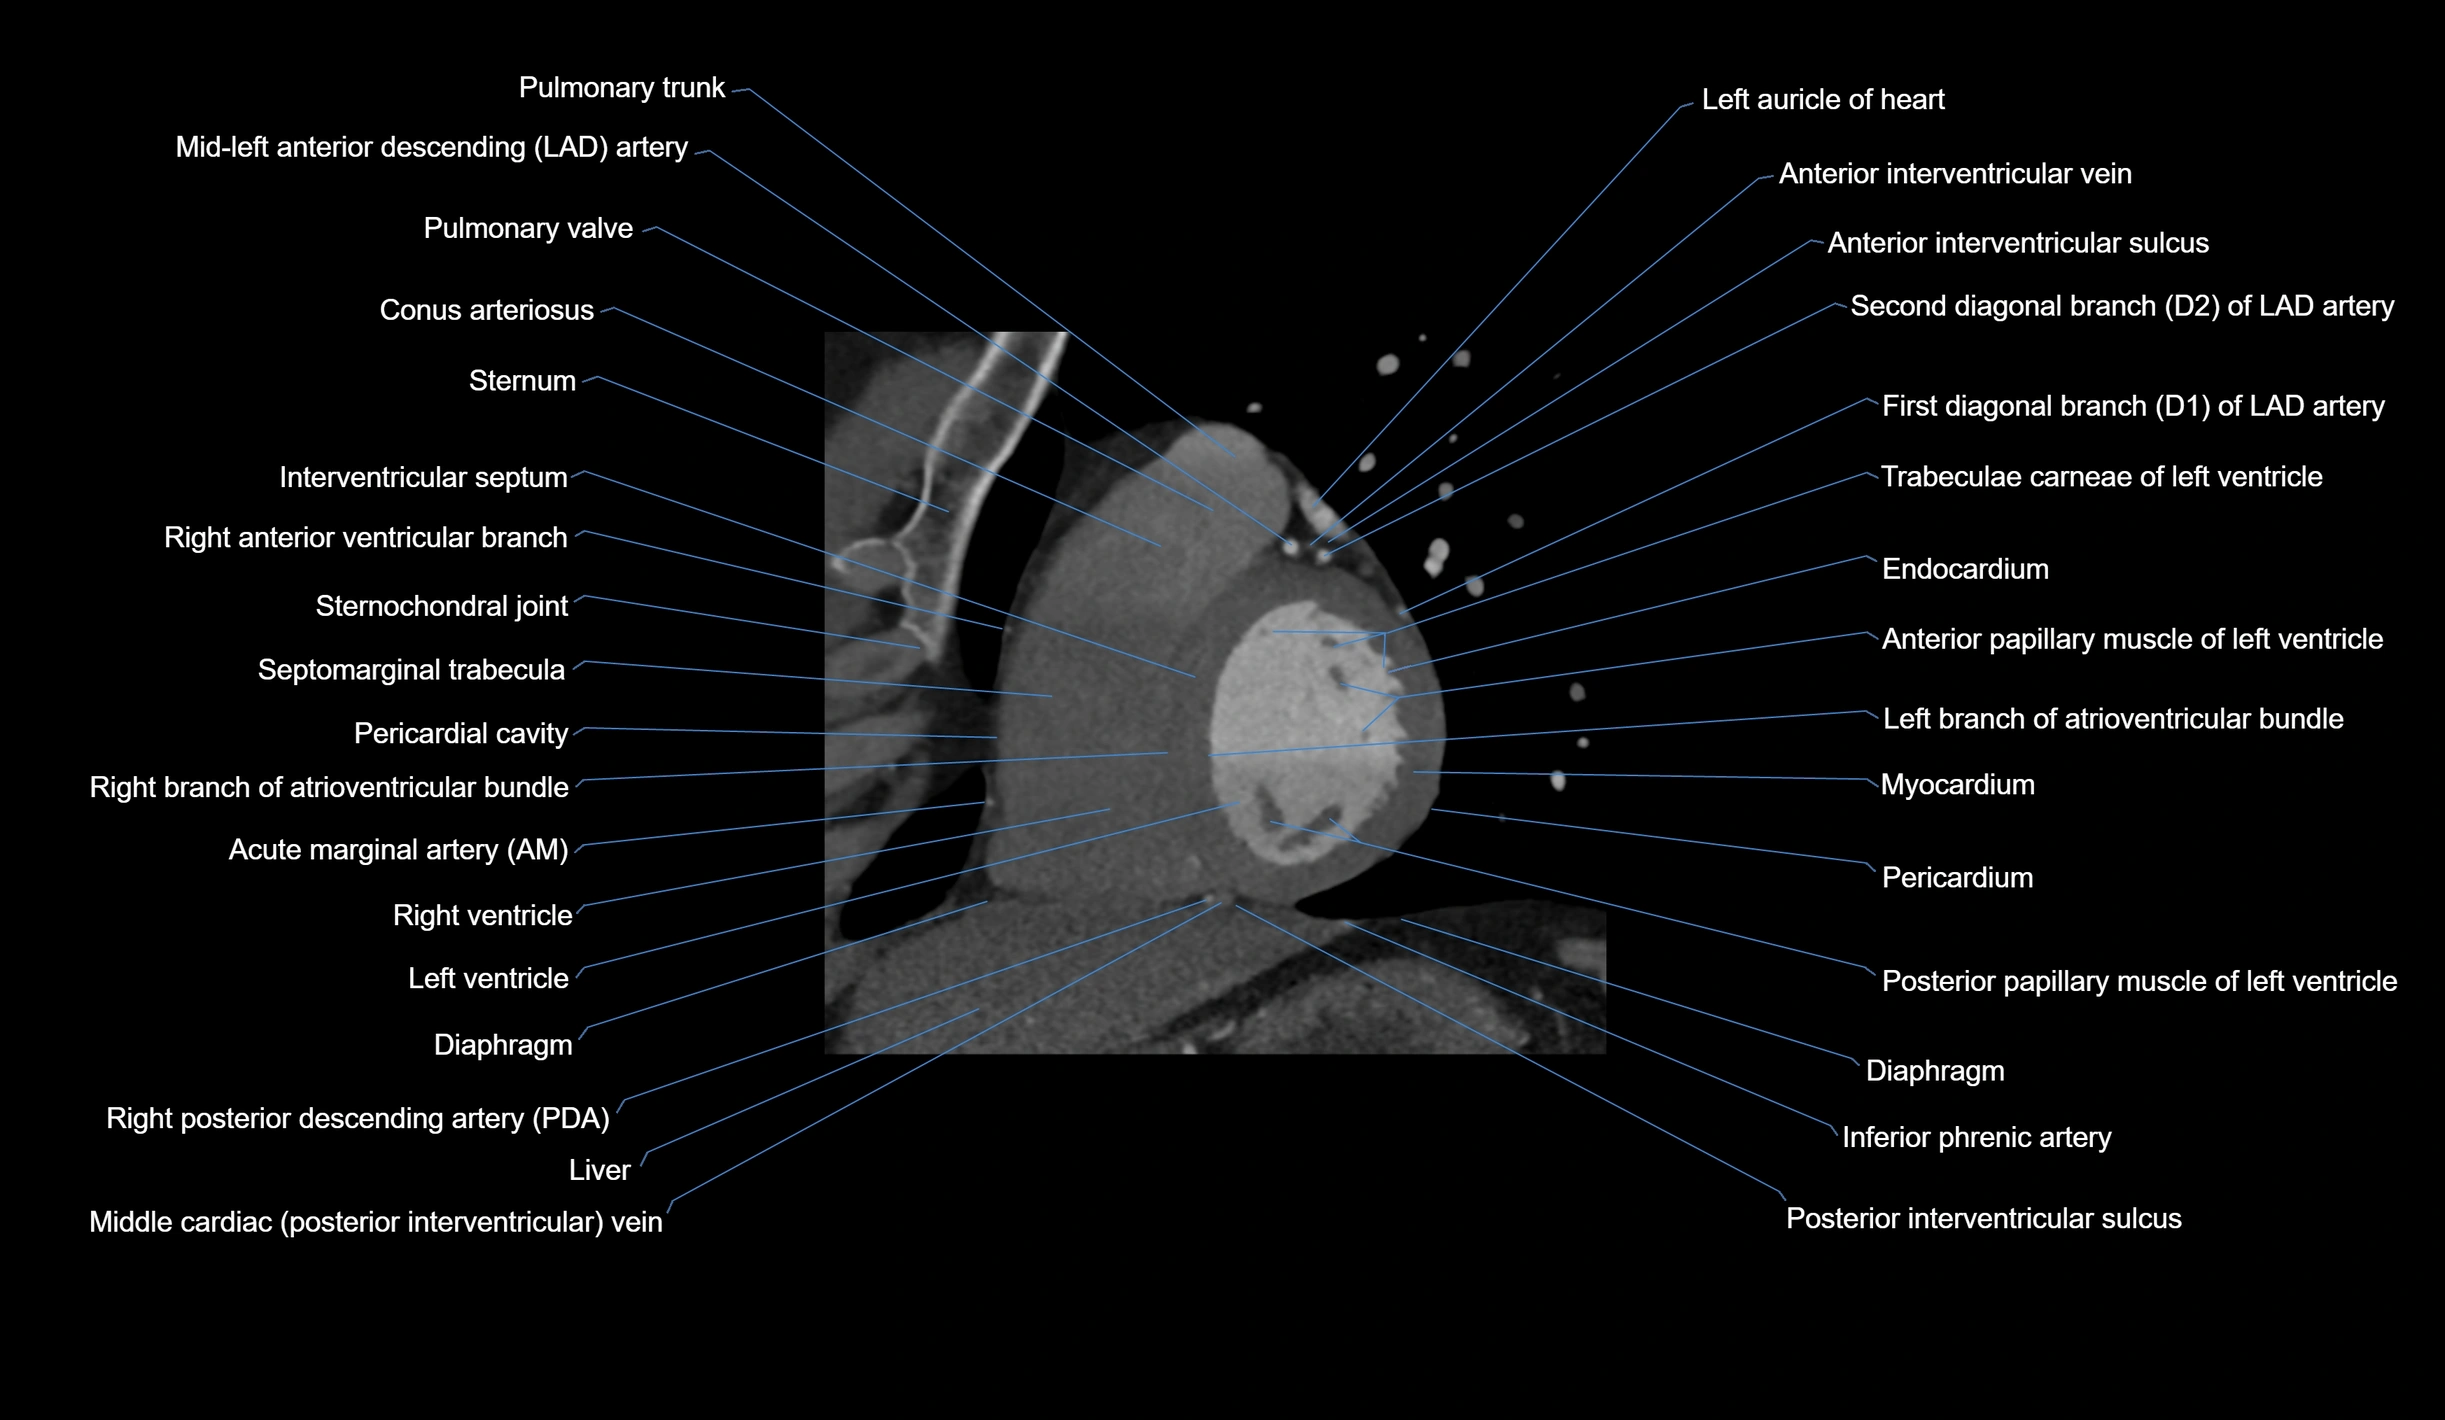

- Acute marginal artery (AM)

- Anterior interventricular sulcus

- Conus arteriosus

- Endocardium

- First diagonal branch (D1) of LAD

- Inferior phrenic artery

- Interventricular Septum

- Left anterior descending artery (LAD)

- Left branch of atrioventricular bundle

- Left ventricle

- Myocardium

- Pericardium

- Posterior interventricular sulcus

- Pulmonary trunk

- Pulmonary valve

- Right branch of atrioventricular bundle

- Right posterior descending coronary artery (Right PDA)

- Right ventricle

- Second diagonal branch (D2) of LAD